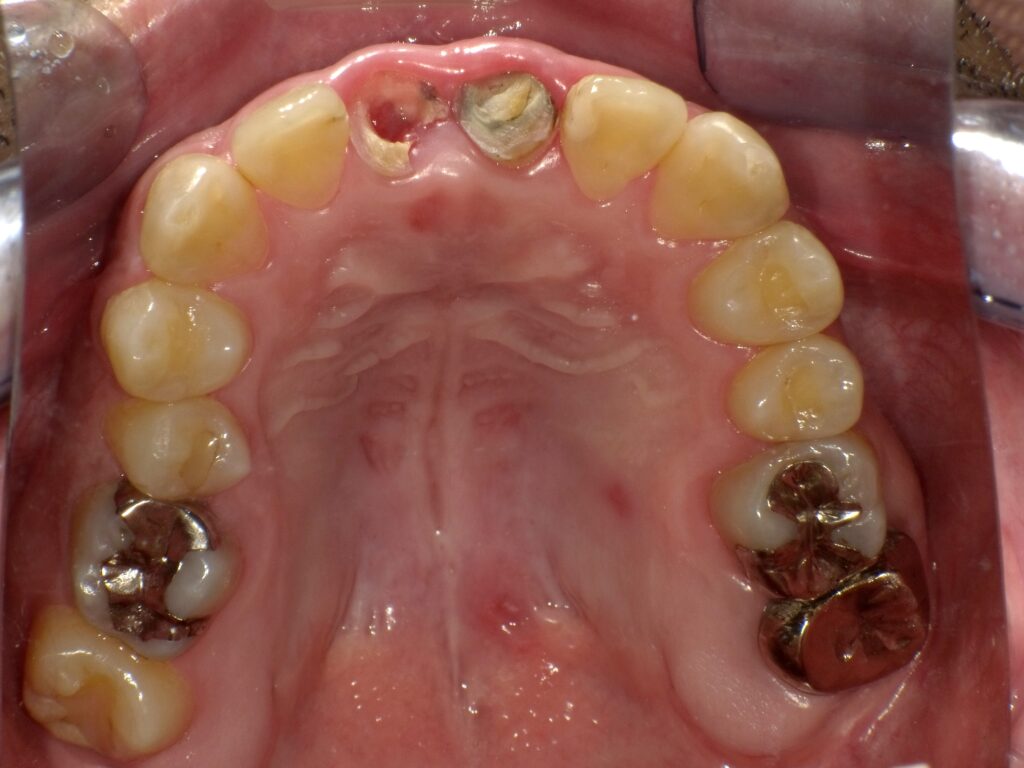

症例一覧 インプラント症例3 2024.11.25 治療内容インプラント主訴前歯部折れたのでインプラント治療を行いたい費用¥1259,500(2本)治療期間治療期間 7ヶ月 インビザライン症例1 前の記事 インプラント症例2 次の記事